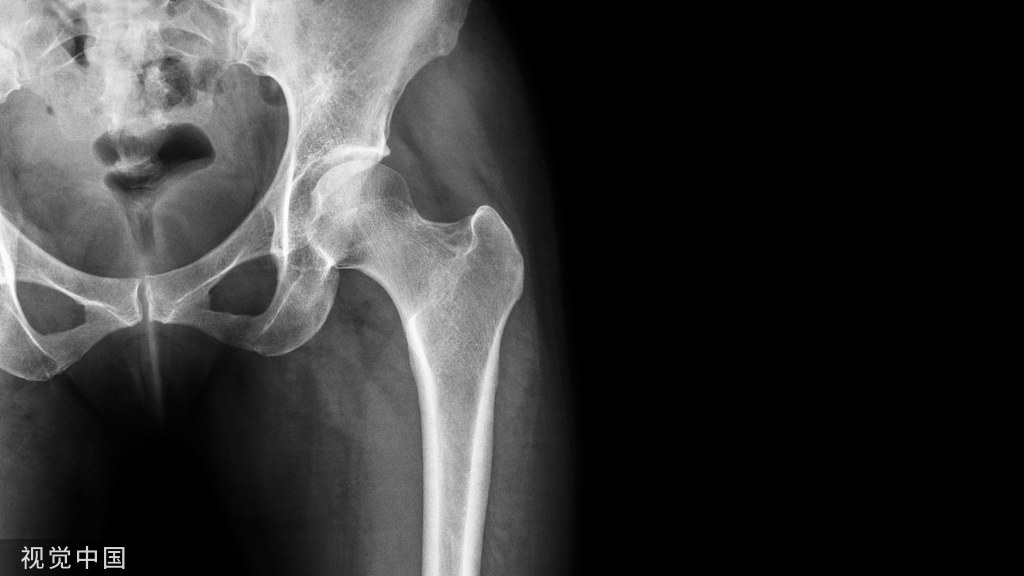

距骨----是一个很厉害的骨也是一个很烦人的骨

厉害在哪里?全身的重量都传导到它一个骨进行负重

烦人在哪里?你知道它有多少关节面呢??60%都是关节面!胫距关节、距下关节、距舟关节

距骨与跟骨接触就有三个关节面如果想要好的功能那么这三个关节面最好都是解剖复位

还有一个就是血供的影响距骨很容易坏死就是血供遭到了破坏

最主要的血供包括前方胫前动脉内侧胫后动脉外侧腓动脉的分支(跗骨窦)